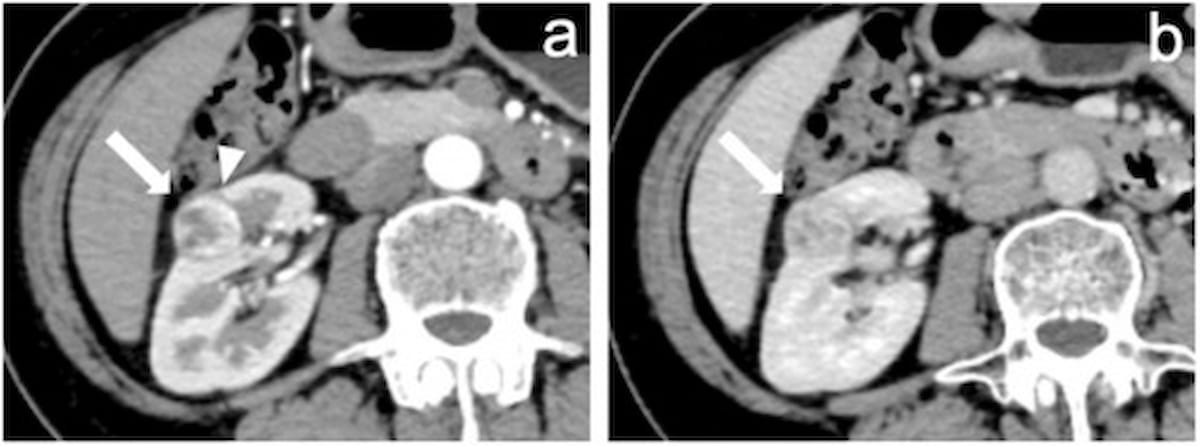

Emerging research suggests that a computed tomography (CT)-based radiomics model can predict FOXM1 expression and is independently prognostic for clear cell renal cell carcinoma.